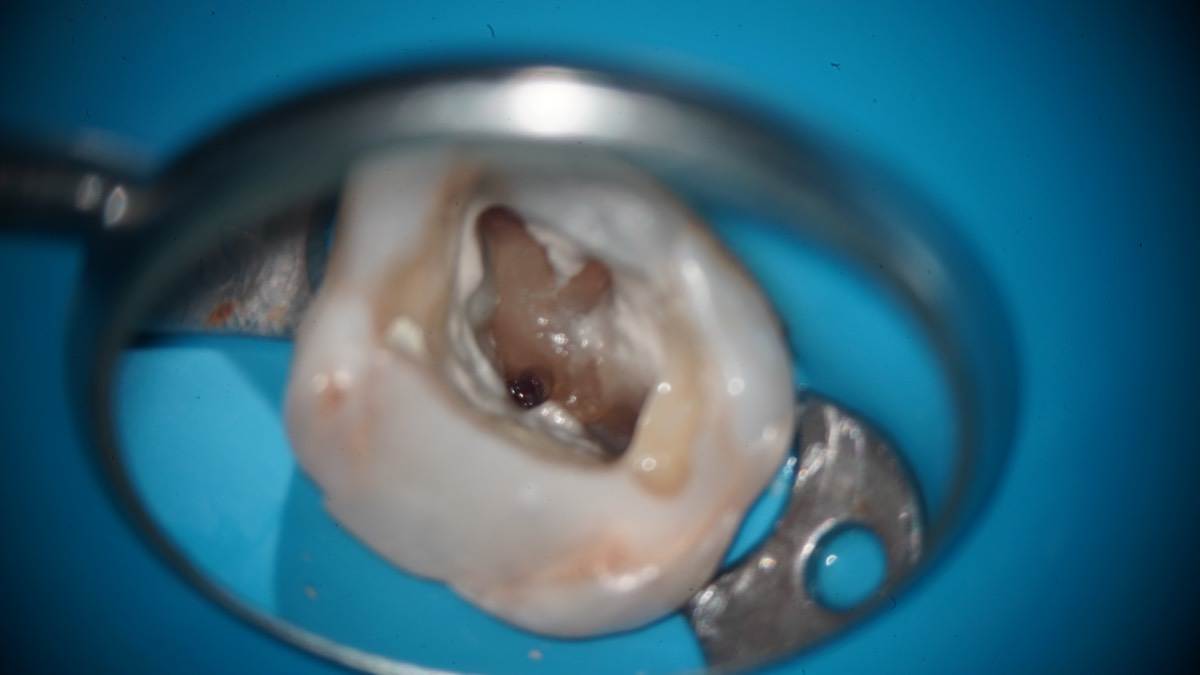

Гарриевич Опубликовано 7 апреля Автор Поделиться Опубликовано 7 апреля Извлечение двух фрагментов сломанных инструментов из одного зуба:) И если кому интересно, то вот полный фотопротокол 3 Ссылка на комментарий

Гарриевич Опубликовано 13 марта Автор Поделиться Опубликовано 13 марта (изменено) Изменено 13 марта пользователем Гарриевич 2 1 1 Ссылка на комментарий